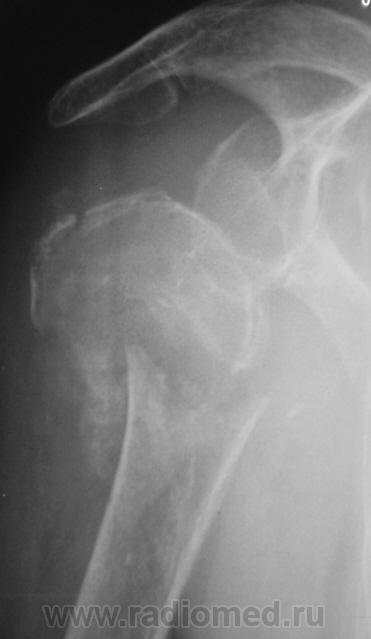

Травма. Пациентка "преклонного" возраста направлена на рентгенографию плечевого сустава.

головки плечевой кости. Вопрос только в том. будет ли этот прелом на фоне остеопороза или пат. изменённой костной ткани?

Вероятно перелом патологический, на фоне метастатического поражения. Показана рентгенография таза, черепа.

В лёгких (кусок лёгкого виден) синдром диссеминации с обеих сторон по типу карциноматоза.

очень похоже на метастаз рака почки.

Похоже, и на метастаз...